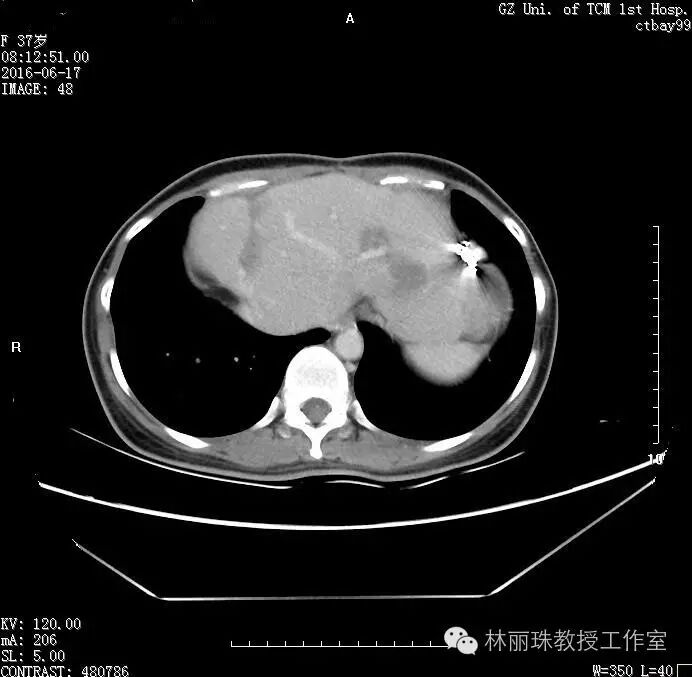

20166月患者复查CT示肝内肿物较前缩小